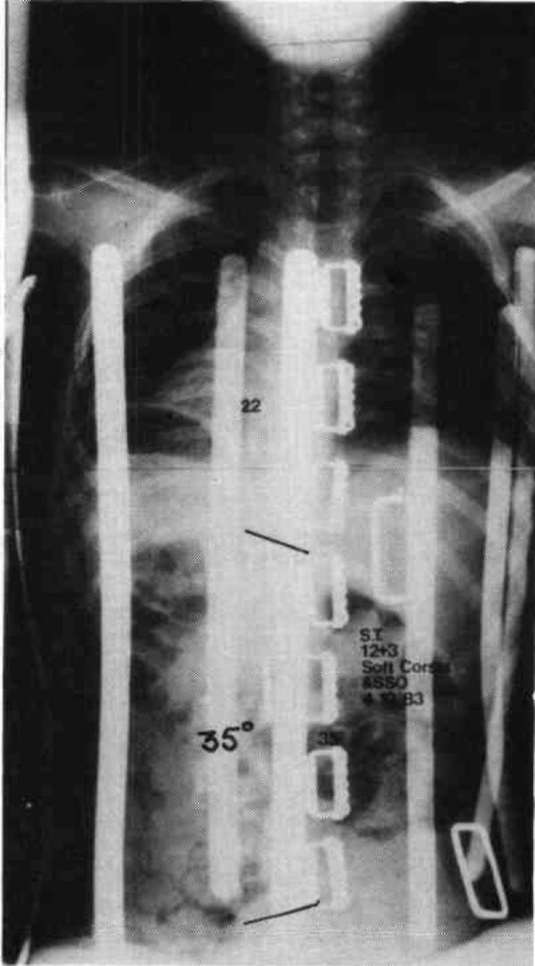

Let us now look at two examples were these stabilizing schemes have been simultaneously applied. Fig. 10a is a photo of a 12 year old boy with muscular dystrophy, sitting as he was presented to us. Fig. 10b shows the sitting support system properly applied. The corset is entirely independent; it is not attached to the seat. Fig. 10c and Fig. 10d compare his A-P spine x-rays without and with the orthotic system. The lateral tilt of his pelvis is reduced from 30 degrees to 14 degrees. The Cobb angle of his scoliosis was reduced from 65 degrees to 35 degrees. Curve control of this magnitude is not unusual as long as the deformity is still flexible. Fig. 11a is the x-ray of J.S., a 14 year old girl with cerebral palsy. She presented a right thoraco-lumbar scoliosis of 38 degrees and a rightward pelvic tilt of 8 degrees. Her shoulders were tilted 13 degrees to the left partly because she used her right arm for propping to avoid falling to the right. We provided her with a soft corset and the Gillette Sitting Support Orthosis. The Sitting Support Orthosis was to provide pelvic control and bilateral "propping" support. It had no head rest or anterior support. The x-ray taken just after fitting shows pelvic tilt reduced to 2 degrees (Fig. 11b), the Cobb angle of the scoliosis reduced to 22 degrees, and shoulders leveled. Both hands were free to function, and she said she could breathe deeper.

Figure 11a. X-ray of J.S., a 14 year old girl with cerebral palsy.

Figure 11b. J.S. provided with a soft corset and the Gillette Sitting Support Orthosis.